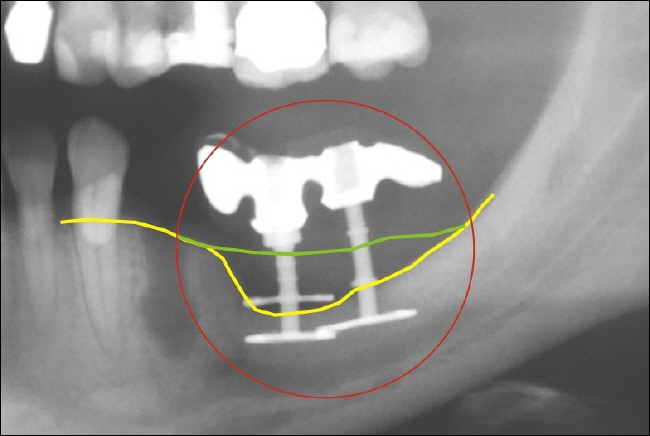

Knochenabbau Die Röntgenaufnahme zeigt den massiven Knochenverlust an zwei Diskimplantaten (zwischen der grünen und der gelben Linie). Die gelbe Linie zeigt den aktuellen Knochenverlauf, die grüne demonstriert den ursprünglichen. Die obere Scheibe an dem linken Diskimplantat ist gar nicht mehr von Knochen umgeben. Die Implantate sollten entfernt werden, um weiteren Knochenabbau zu verhindern.